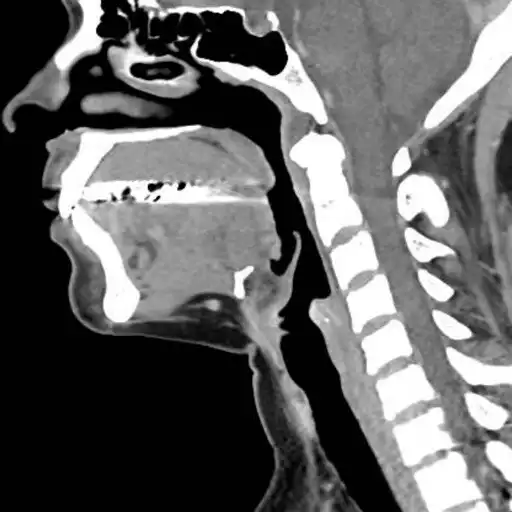

This app provides a dynamic and interactive method of viewing cross-sectional human anatomy on computed tomography (CT). The information contained in this app cannot be guaranteed for completeness and accuracy.

- Labeling of anatomical parts

- 3D Anatomic localization